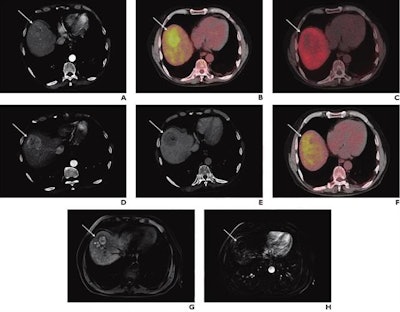

A 74-year-old man with known liver cirrhosis. The patient underwent multiphase contrast-enhanced CT. A lesion in the liver dose (arrow) shows hyperenhancement in the arterial phase (A) and washout in the delayed phase (not shown), consistent with hepatocellular carcinoma. The lesion also shows marked hypermetabolism on FDG-PET/CT (B) but not on F-18 FCH PET/CT (C). The patient underwent multiphase contrast-enhanced CT and FDG-PET/CT one month after radioembolization. The lesion was stable in size and demonstrated persistent hyperenhancement in the arterial phase (D) and washout in the delayed phase (E) but a complete response on FDG-PET/CT (F). The patient underwent MRI six months after the procedure. The lesion shows complete response according to mRECIST, including hyperintensity on unenhanced fat-suppressed T1-weighted imaging (G), without internal enhancement on the subtracted arterial-phase image (H). Image courtesy of the American Journal of Roentgenology.Early PET/CT response was significantly associated with prolonged overall survival on univariable (hazard ratio = 0.37) and multivariable analyses (hazard ratio = 0.24), the group found.